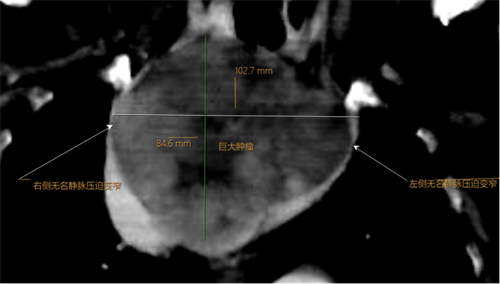

术前CT显示:纵膈巨大占位大小约为10.2cm*9.0cm*8.5cm,邻近气管及大血管明显受压变窄,气管前后径仅为2.5mm(正常成人气管直径约15-25mm)

据了解,李奶奶曾被诊断患有胸腺瘤,多次前往四川省人民医院及四川大学华西医院就诊。由于其身体基础状况较差,且肿瘤巨大(已侵犯大血管及气管),外科切除难度极大,手术风险极高,李奶奶本人也拒绝外科手术切除。此次,因巨大的胸腺肿瘤同时压迫气道和右侧无名静脉,导致李奶奶出现急性呼吸困难和上腔静脉血液回流受阻而昏倒。